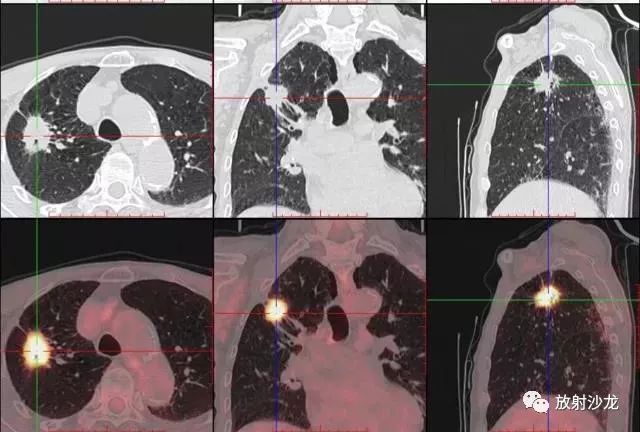

PET-CT是目前世界上最先進(jìn)的核醫(yī)學(xué)分子影像設(shè)備,中文稱(chēng)為正電子發(fā)射計(jì)算機(jī)斷層/X 線(xiàn)計(jì)算機(jī)體層成像。

PET-CT等于PET+CT,包含PET(功能分子影像)與CT(解剖影像)的最優(yōu)化組合;即同時(shí)具有PET和CT的功能,但它絕不是二者功能的簡(jiǎn)單疊加,因?yàn)镻ET與CT優(yōu)勢(shì)互補(bǔ),“1+1>2”。PET-CT除了具備PET和CT各自的功能外,其獨(dú)有的融合圖像,將PET圖像與CT圖像融合, 可以同時(shí)反映病灶的代謝,可以早期診斷疾病的同時(shí),明顯提高診斷的準(zhǔn)確性。